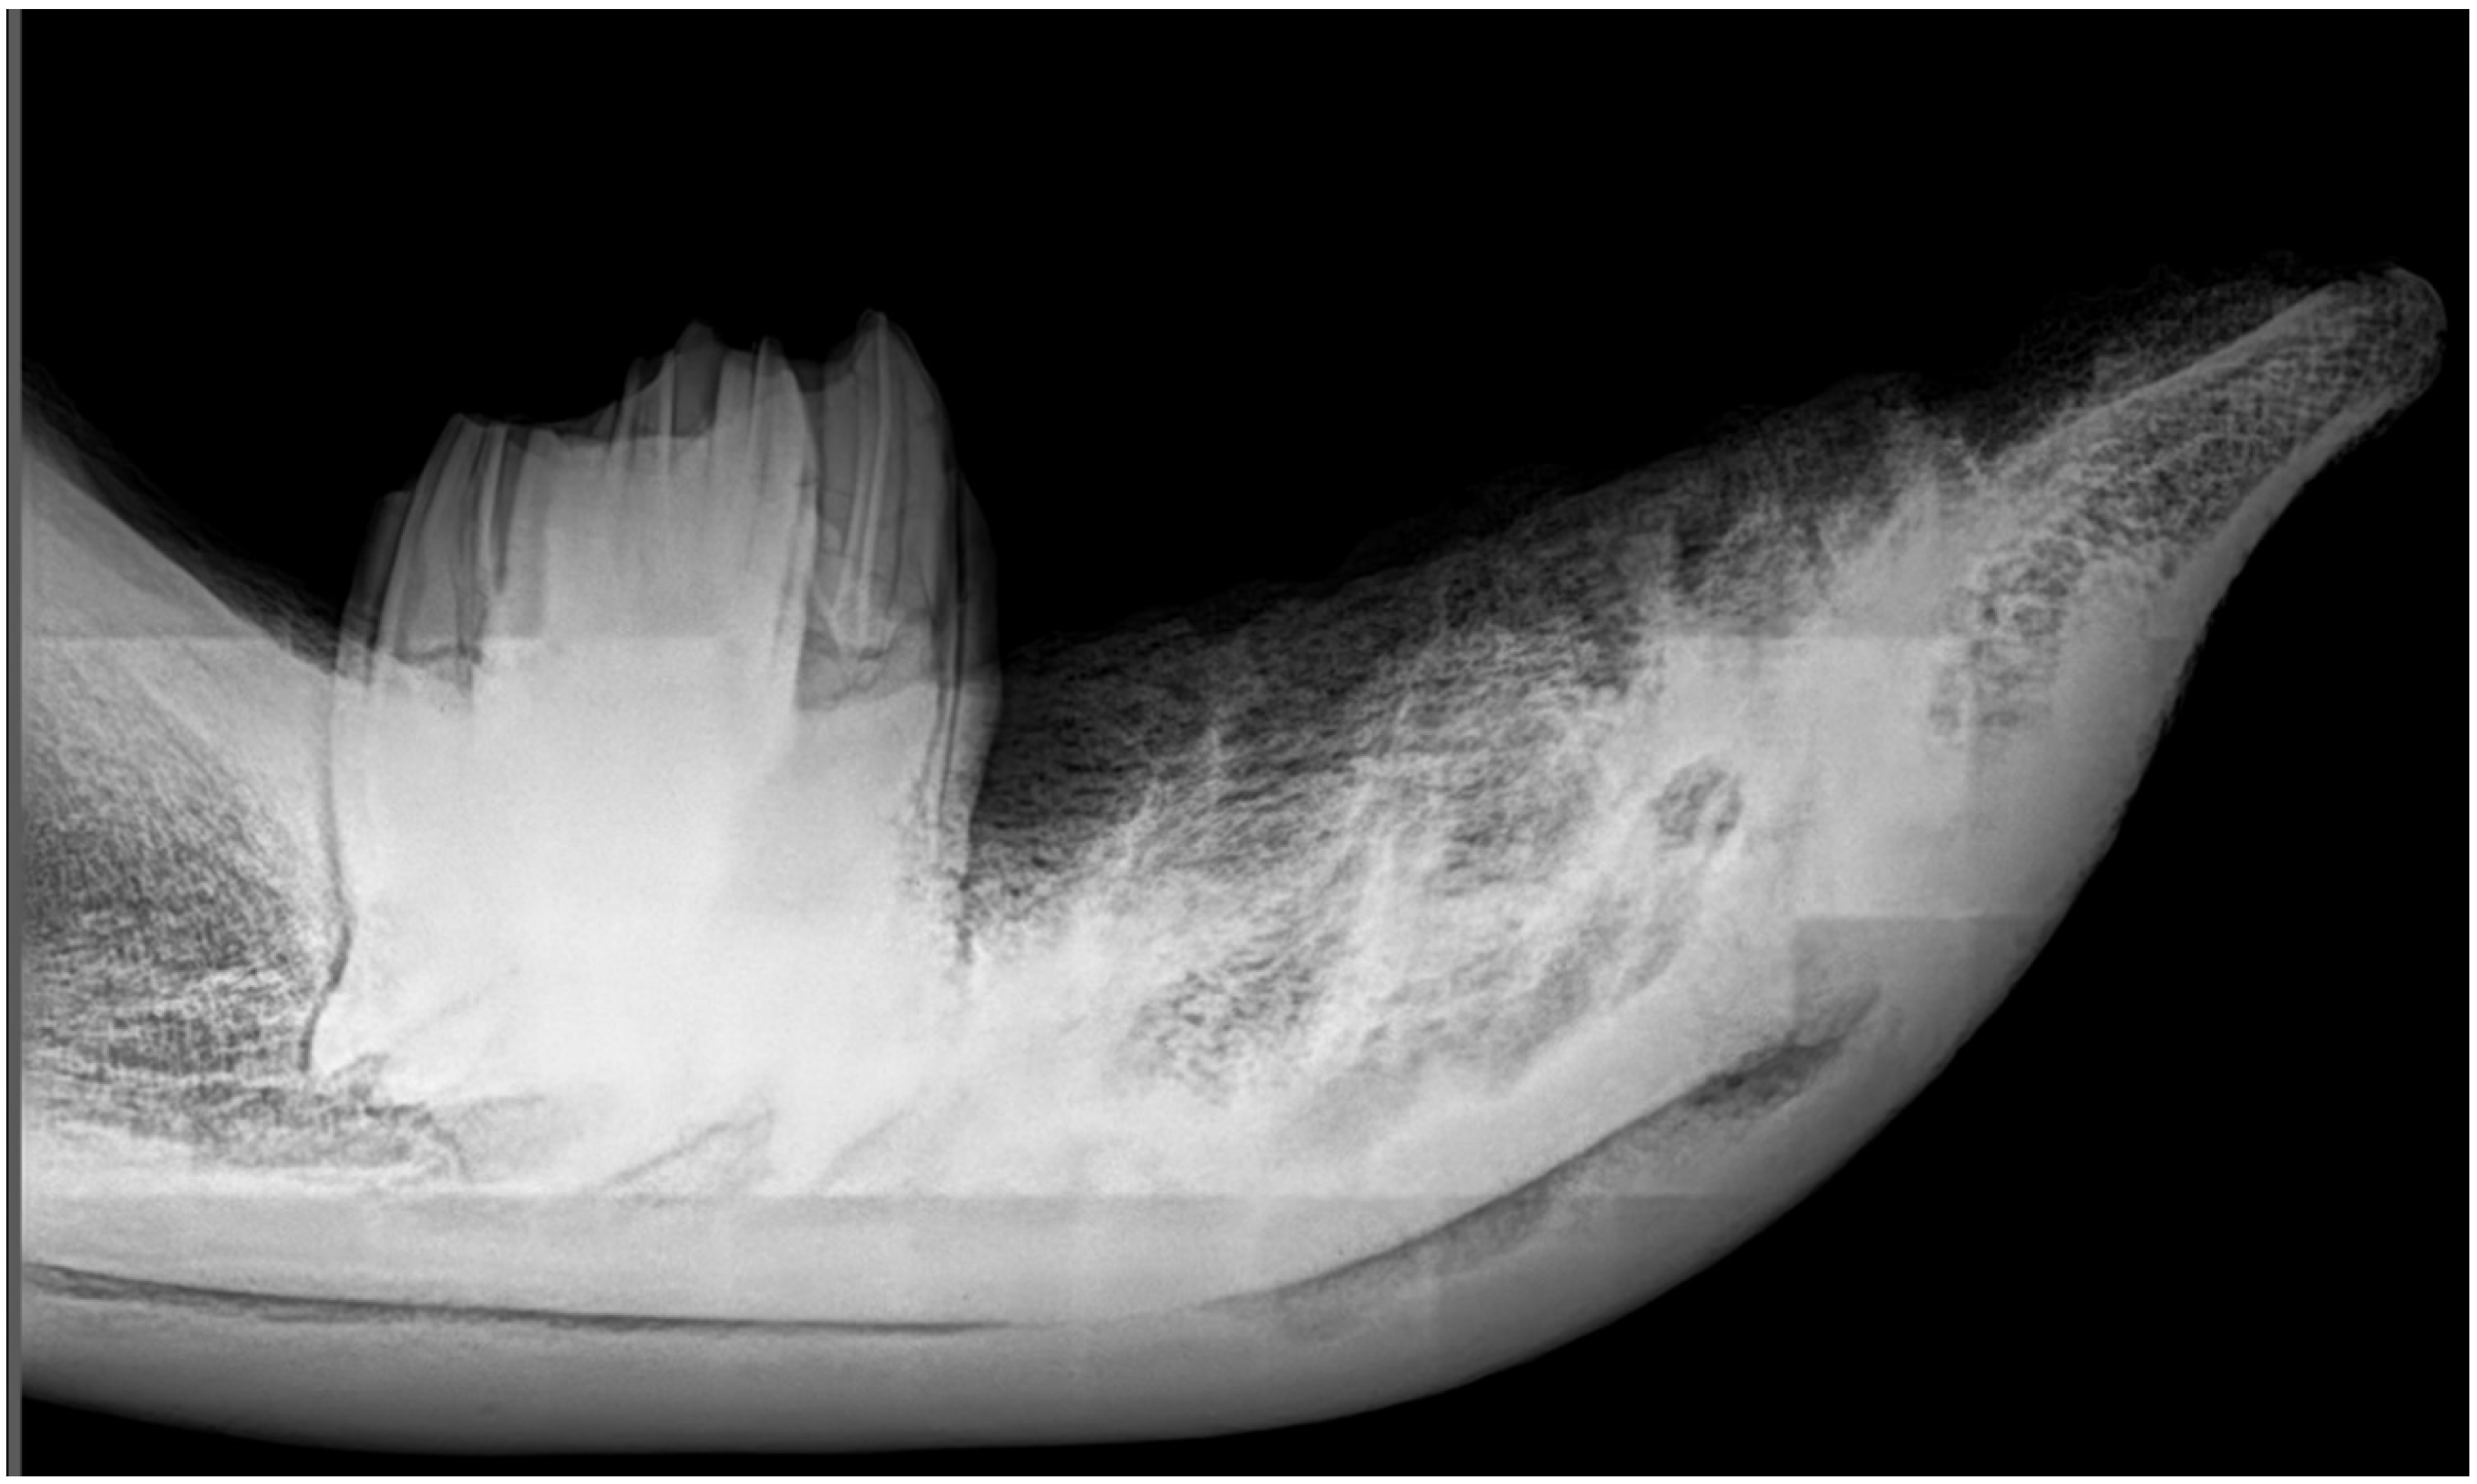

3.3. X-ray Imaging of the Mandible